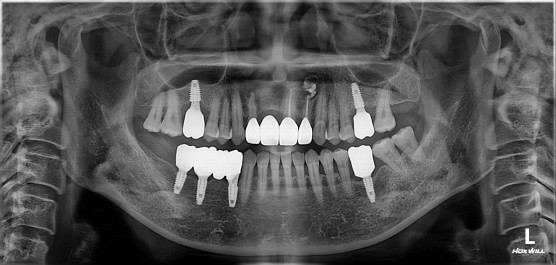

#12X21.22 CR 제작, Fistula 없어짐

[부작용 안내]

신경치료 후 감염, 염증, 통증 등의 부작용이 발생할 수 있으며, 크라운 보철치료 후 부작용은 보철이 잘못 만들어졌을 때 하악 통증, 편두통 등이 있을 수 있습니다. 또 보철 마모 및 탈락이 있을 수 있습니다.